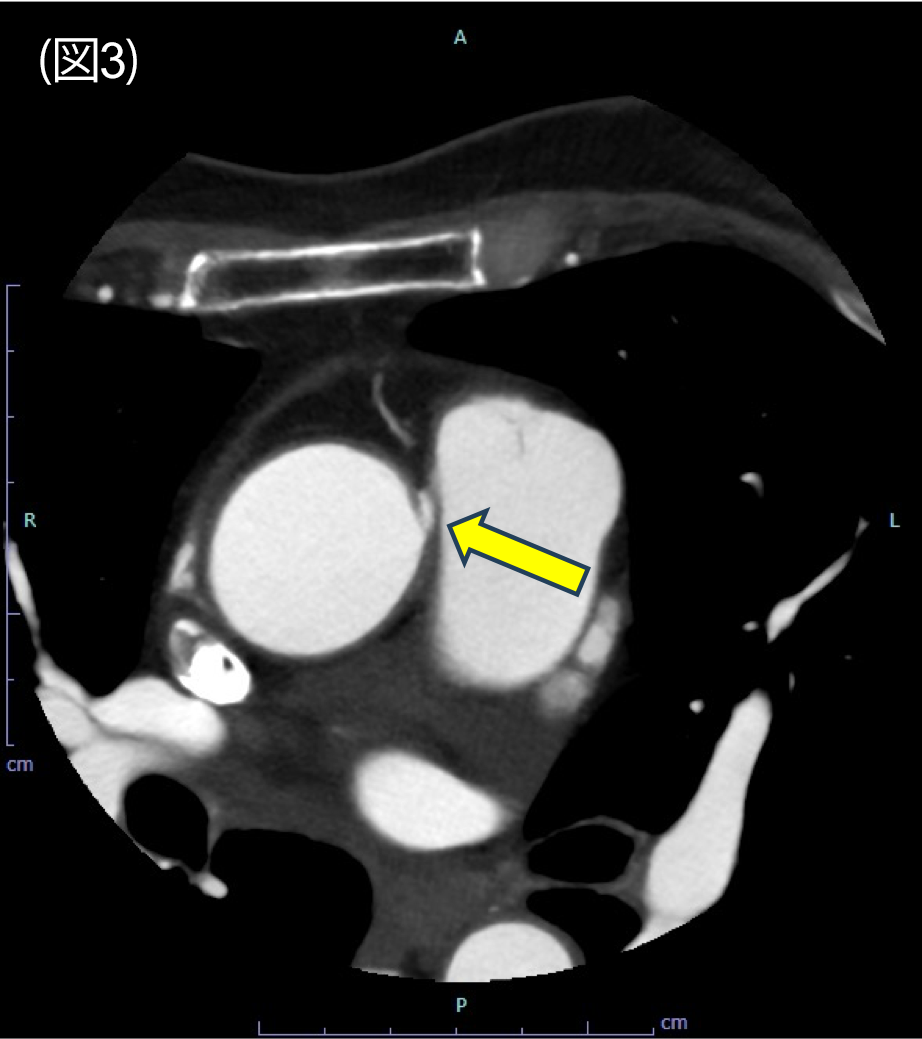

図3.冠動脈CT axial 像

右冠動脈は大動脈と肺動脈の間を走行している。